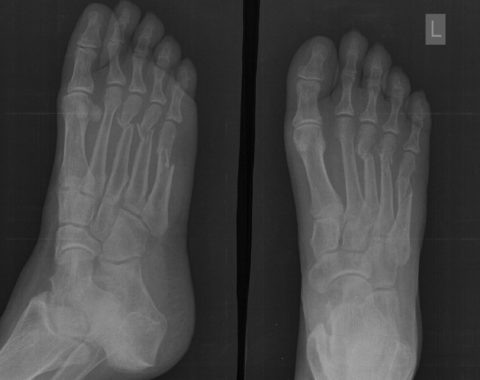

Фото: повреждения голеностопа

Для диагностики назначается рентгенограмма, что должна быть осуществлена в двух или трех проекциях. В зависимости от особенностей лечится подобная травма с помощью открытой или закрытой репозиции. Что касается реабилитационного периода, то для него характерна последующая иммобилизация в течение полутора месяца.

От того, какие бывают переломы стопы, зависит и выбранная методика лечения. Необходимо обратить внимание на то, что для правильного подбора вариантов лечения специалисту необходимо регулярно наблюдать за успешностью восстановления целостности кости с помощью проведения рентгенологических исследований.

В большинстве случаев рентгенологические снимки должны быть проведены сразу в нескольких проекциях для получения более точной и детальной картины травмы.